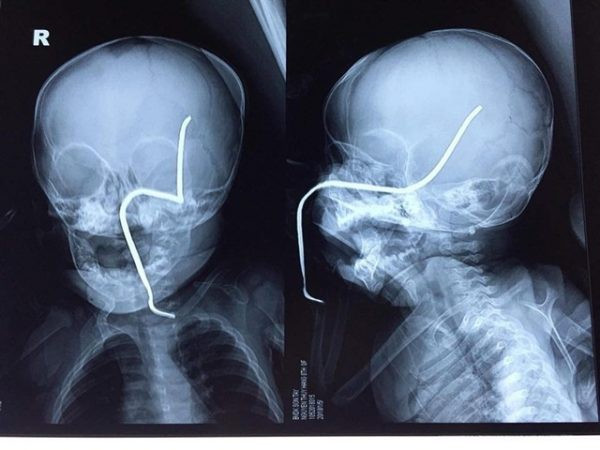

| Hình ảnh phim X-quang của cháu H cho thấy thanh sắt đâm vào gò má trái, xuyên lên vùng não thái dương. |

Theo Ths.Bs Hồ Trung Luân, khoa Ngoại Thần kinh, người trực tiếp phẫu thuật cho bệnh nhi, ca mổ khá khó khăn do thanh sắt đâm vào gò má trái qua tổ chức phần mềm của má, đâm thủng sàn sọ, xuyên qua vùng não thái dương và vùng đỉnh sát các mạch máu lớn.

“Thanh sắt cũ, giòn nên rất dễ gãy, lại nằm sát các mạch máu nên nguy cơ chảy máu trong mổ là rất lớn, đồng thời nguy cơ nhiễm trùng não, áp-xe não cũng rất cao” – BS Luân cho hay.